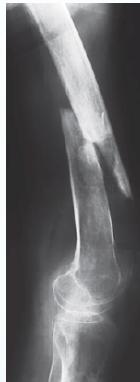

Looser’s zones Z are short lucent bands running through the cortex at right angles, usually going only part way across the bone